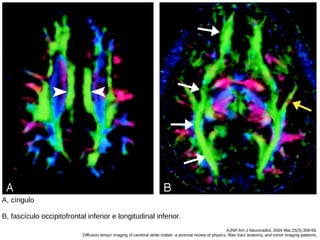

Fascículo occipitofrontal inferior

● Também contecta o frontal com o occipital, mas

abaixo, na borda inferior e lateral do claustrum e

abaixo da ínsula.

● Posteriormente se junta ao longitudinal,

geniculocalcarino para formar o stratum sagital,

um complexo que conecta o lobo occipital ao

restante do cérebro.

● Sua porção média se junta com a porção média

do fascículo uncinado.

Fascículo uncinado

● Gancho, da fissura lateral, que conecta os giros

orbitários e frontal inferior ao lobo temporal

anterior.

AJNR Am J Neuroradiol. 2004 Mar;25(3):356-69.

Diffusion tensor imaging of cerebral white matter: a pictorial review of physics, fiber tract anatomy, and tumor imaging patterns.